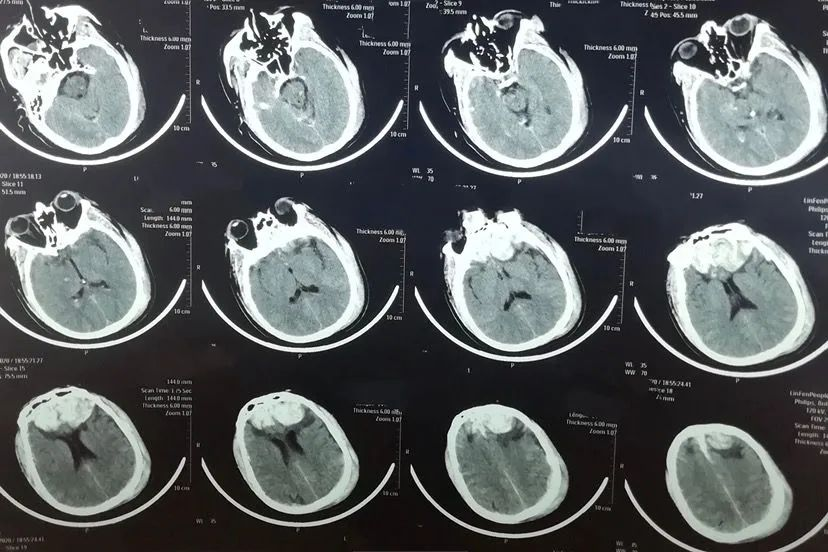

患者男性,48岁。2020年10月头部外伤,头颅CT显示双额叶脑挫裂伤,于当地医院行左额颞开颅血肿清除+去骨瓣减压术。

给予行左额颅骨成形术,术后双侧硬膜下积液消失,但出现脑积水,也就是脑外积水转为脑内积水。